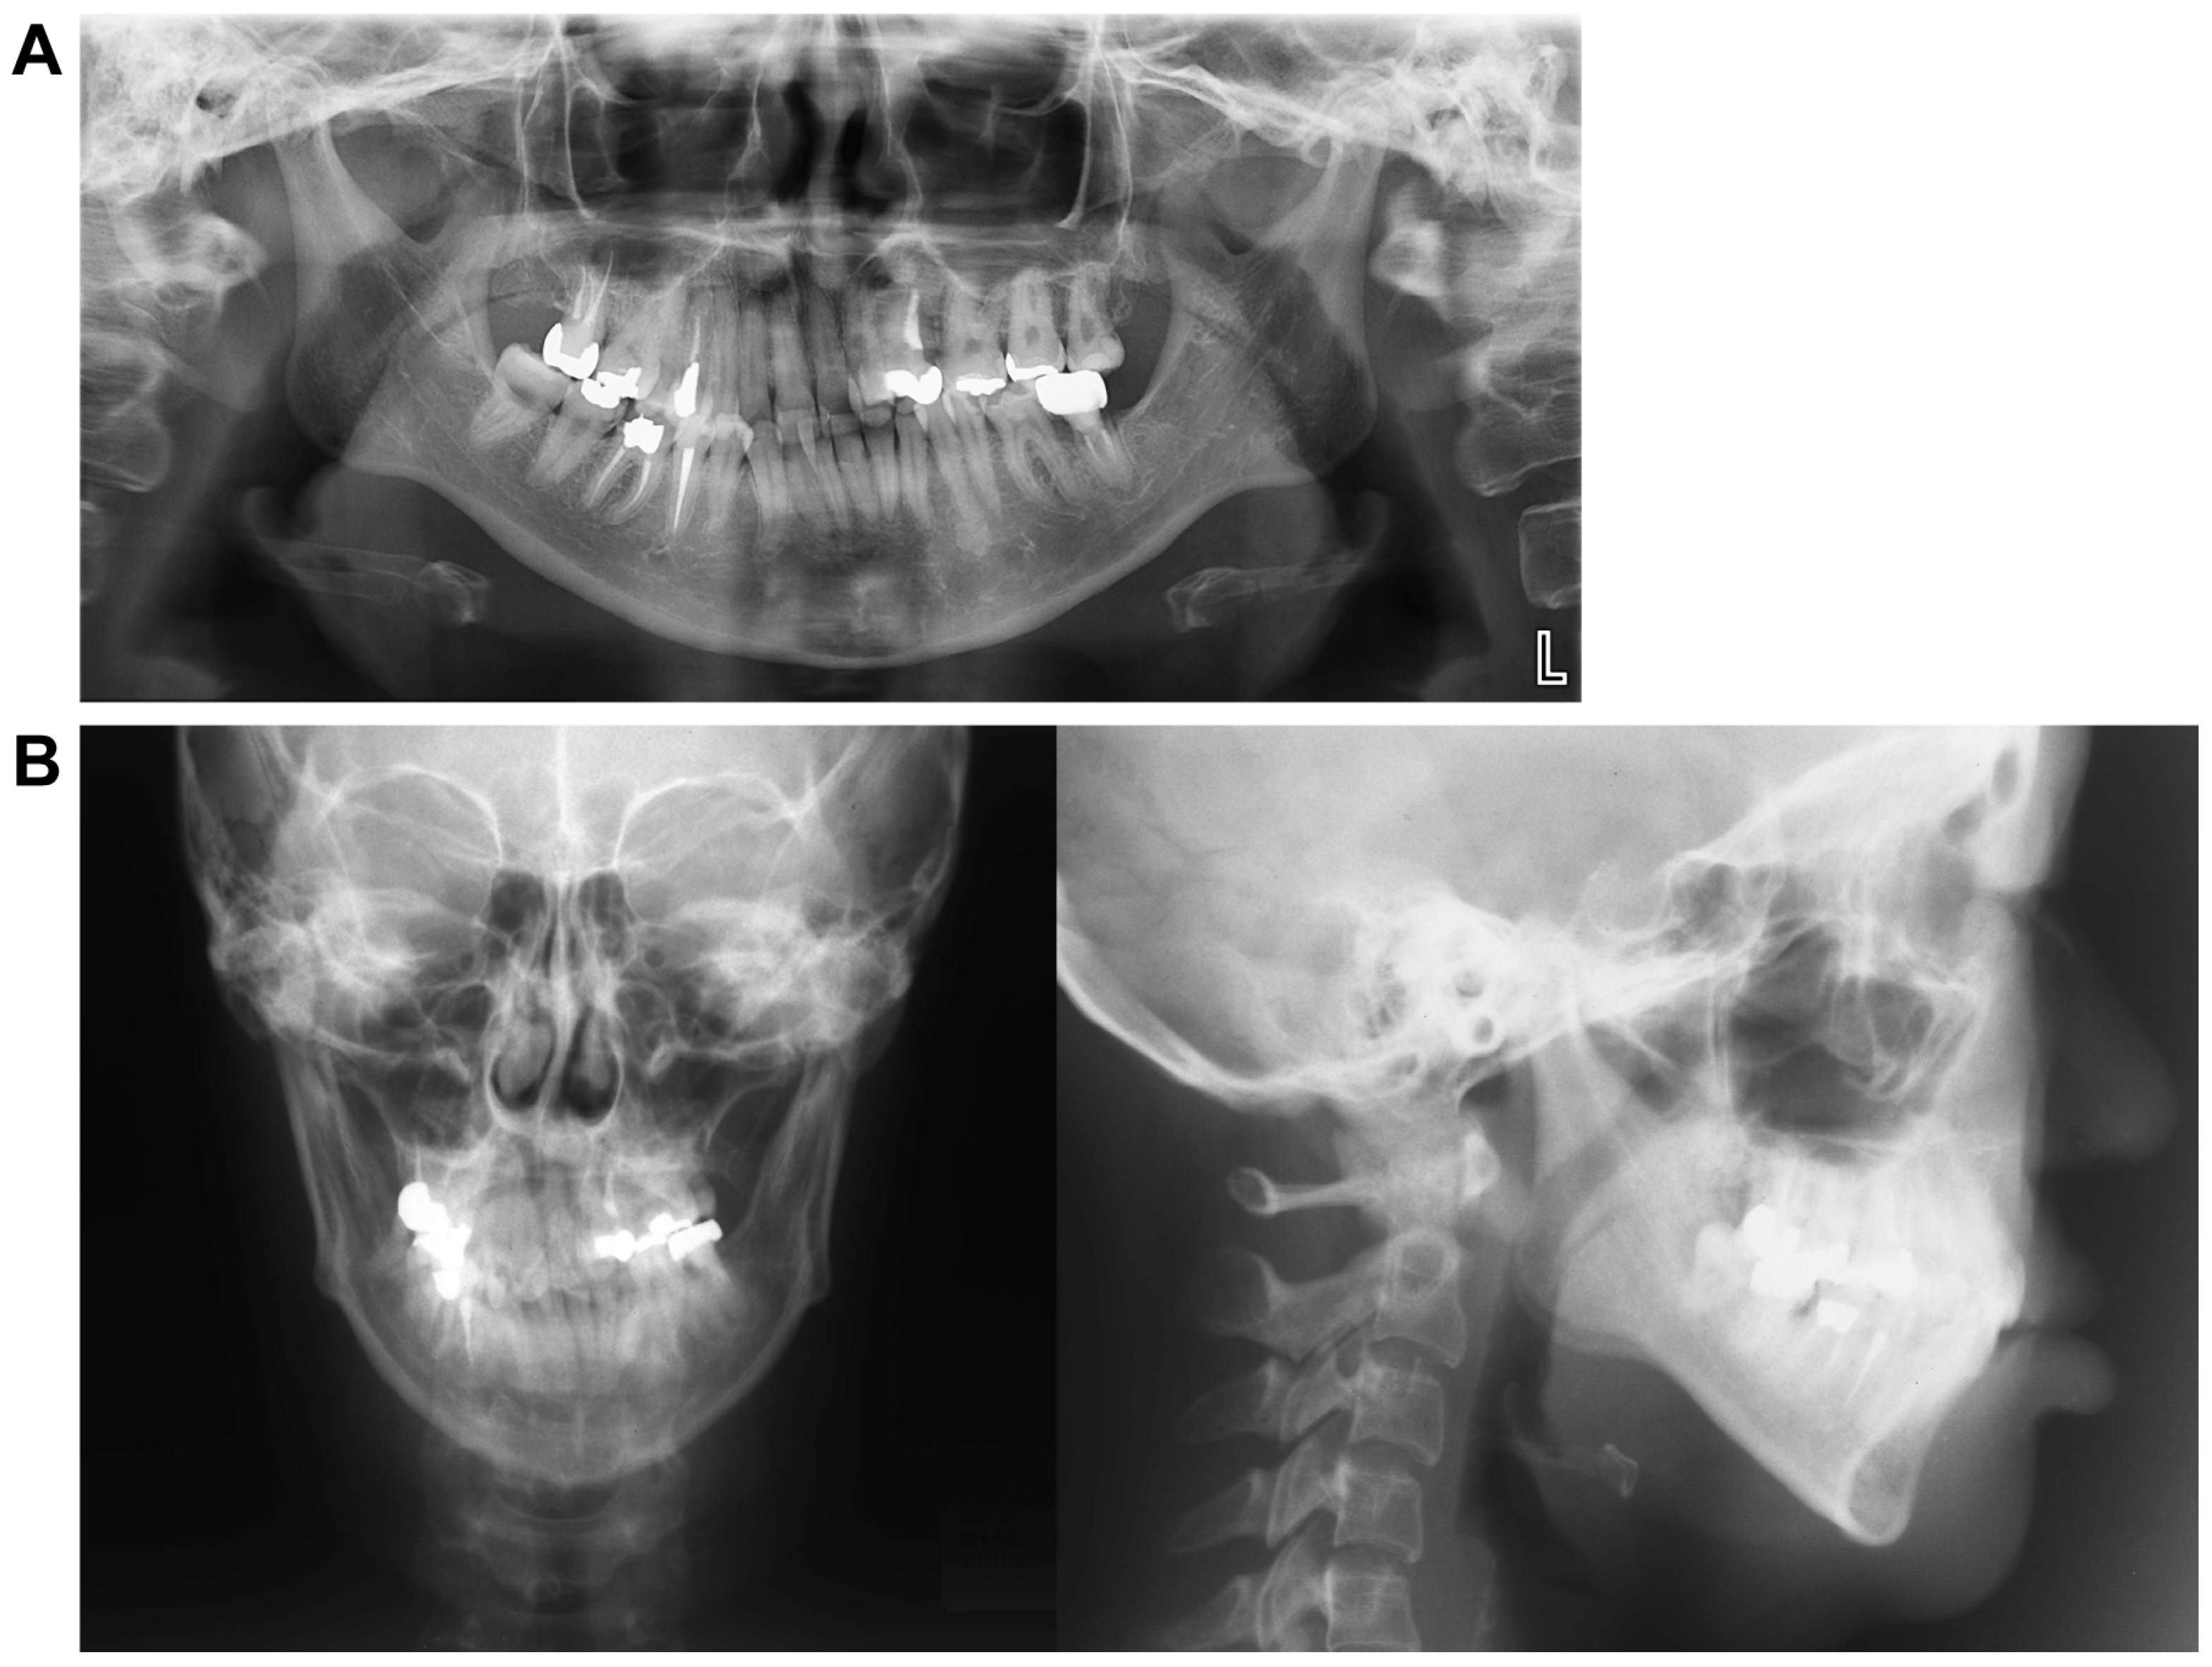

3.3. Panoramic Cephalometric Radiograph (Figure 2A)

In the maxilla, the right first premolar, second molar, and left second premolar had undergone root canal treatment. Similarly, in the mandible, the right second premolar, first molar, and left second molar also underwent root canal treatment. An apical lesion was observed in the mandibular left second molar. Notably, wisdom teeth were present in the left maxillary and right mandibular regions. However, there was minimal curvature of the teeth roots, and the alveolar bone level appeared normal throughout the dentition.

Figure 2.

Pre-treatment record. (A) Panoramic radiograph. (B) Lateral and front cephalogram.